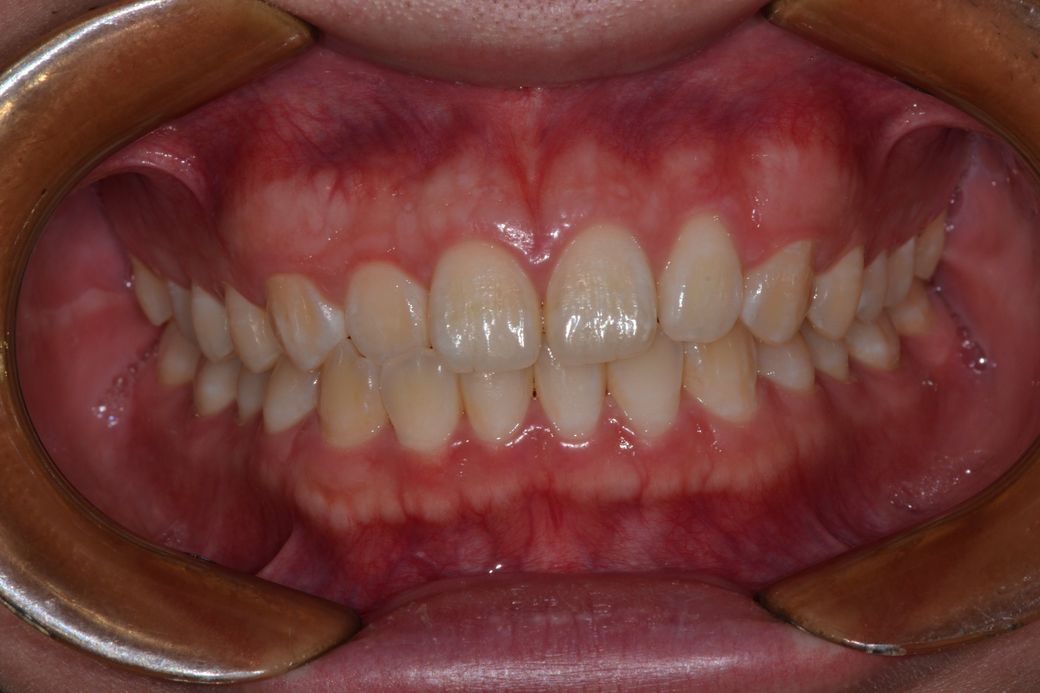

어금니 교합 및 치아 치열, 전체 교합이 잘맞는건지 알고싶어요

#치아 앞쪽?이 부딪히는곳에 가끔 통증이있어요 이유를 모르겠어요

#치아에 하얀색 점같은거는 어떻게 제거하나요?

치아에 있는 하얀점은 치아 발육시 생긴 것으로 미용상으로는 좋지 않지만 그냥 두어도 됩니다.

치아표면에 있는 하얀식 반점은 반상치일수도 있고, 초기 치아탈회의 경우도 있습니다.현재로서 치료가 필요하지는 않은것으로 보입니다. 감사합니다.

사진 자료만으로는 정확한 판단이 힘들며 CO, CR 등의 재현성 등을 체크해보아야할 것으로 보입니다. 물론 말씀하신 것처럼 좌우가 맞물리는 정도가 조금 다르긴 하나 대부분 사람들은 완전히 대칭을 이루기는 쉽지 않습니다. 따라서 일상생활에 불편감이 없거나 치열로 인하여 심미적으로 문제가 되지 않는 범위라면 특별히 치료를 하지 않아도 될 것으로 보입니다.